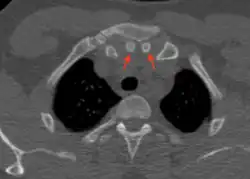

Axial computed tomography showing the episternal ossicles (red arrows)

Episternal ossicles (or suprasternal ossicles) are small bones that are sometimes present at the upper end of the chest bone. The prevalence of these ossicles is around 1.5%.[1]

The episternal ossicles are oval-shaped bones that are occasionally found at the superior and posterior border of the manubrium. The episternal ossicles were first described by Cobb in 1937.[2] They may be present unilaterally or bilaterally.[3] Its size ranges from 2–15 mm depending on individuals.[4] These ossicles are asymptomatic and does not cause any harm, although it may be diagnosed as fracture, vascular ossification or calcified lymph nodes.